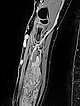

T1-weighted, fat-saturated, contrast-enhanced MRI sequence of the forearm.

The complete enhancement of the malformation in the musculature can clearly be seen. Therefore this is a venous malformation.

Some rather enlarged dysplastic veins are also found laterally on the proximal forearm epifascially in the subcutaneous fat tissue.